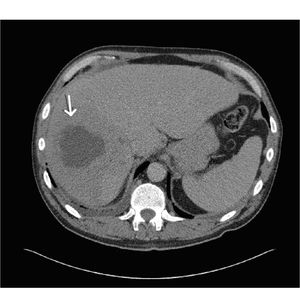

He was resuscitated with intravenous fluids and blood transfusion. Working on a diagnosis of haematological malignancy, a bone marrow aspirate and biopsy were performed; there were both normal. An abdominal CT scan though showed a 5.7cm in diameter hypodense lesion in the right lobe of the liver, suggestive of a liver abscess (Figure 1). An area of thickening was noted in the pelvis, together with a right side basal effusion and a dilated left ureter.